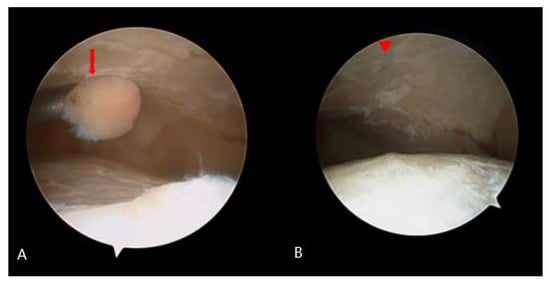

2.2. Surgical Procedure

2.3. Postoperative Care